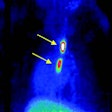

PET agent could advance blood clot imaging